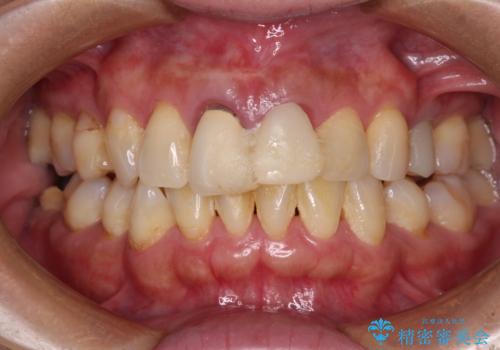

- 治療中の前歯の仮歯がひどい状態であるとのことで来院された患者様です。

治療中の前歯は根管治療の途中であり、根尖部に痛みを感じる状態でした。

まずは審美的な仮歯を装着し、根管治療を行った後にオールセラミッククラウンにて補綴治療を行うこととしました。